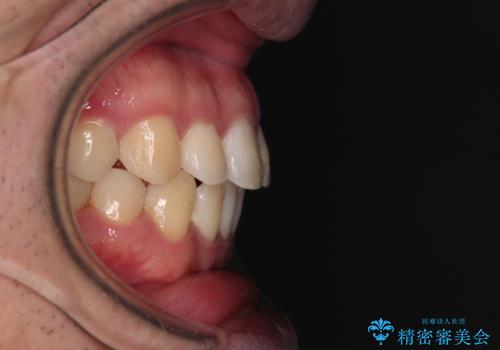

インビザラインで奥歯の咬み合わせと前歯のデコボコを改善

- 前歯のデコボコと奥歯の咬み合わせを気にして来院された患者様です。

前歯のデコボコはインビザラインで十分に対応可能と判断できましたが、咬合力が強いため、臼歯(特に右側)の交叉咬合はインビザライン単体では困難と思われました。

まずはインビザライン単体で矯正治療を開始し、交叉咬合が改善されない場合にはアンカースクリューなどの使用を検討することとしました。

インビザライン単体では右側の交叉咬合を解消することができなかったため、アンカースクリューを併用して咬合を改善させました。